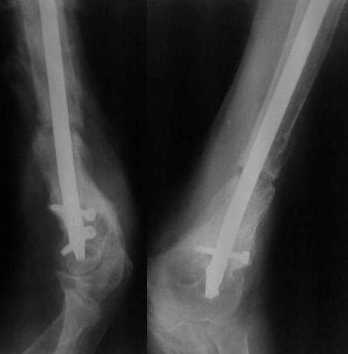

Неудачный остеосинтез пластиной: поломка винтов, миграция фиксатора. После удаления пластины сформировался гипопластический ложный сустав нижней трети бедренной кости, укорочение н/к 5 см. Выполнялся дистакционный остеосинтез аппратом Илизарова на штифте. Зона ложного сустава "не открывалась". Через 10 месяцев, когда даже регенерат полностью перестроился, консолидации в зоне ложного сустава не наступило, несмотря на стабильную фиксацию и постоянную компрессию(штифт+аппрата на 4 кольцах).